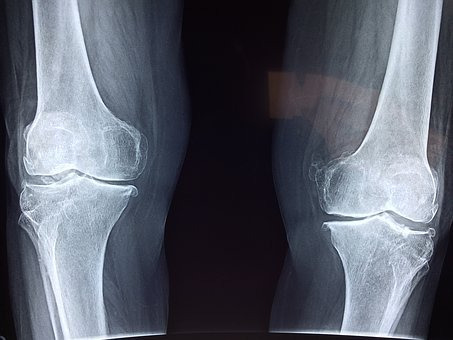

1. 연골노화

연골이 얇아져서 작은 충격이나 과도한 움직임에도 큰 통증을 초래하게 되는 연골노화 증상은

시기의 차이는 있지만 거의 모든 사람들이 피할 수 없는 무릎 연골 손상 증상입니다.

대게는 60대에 본격적으로 연골 노화가 시작되는데 이 시기에는 바닥에 앉을때 무릎 꿇는 자세는 절대 피해야 하고 운동을 할때에도 무릎이 바닥에 닿는 자세는 피해야 합니다. 또한 계단을 오르고 내리는 것 역시 피하며 자극을 주지 않고 무릎 연골 손상 증상의 완화 및 진행 속도를 최대한 낮춰주어야 합니다.